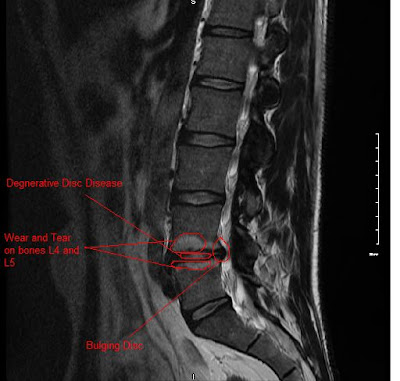

Below is an MRI scan of my back, prior to surgery. I've added some comments to it:-

(MRI courtesy of Boulder Community Hospital)